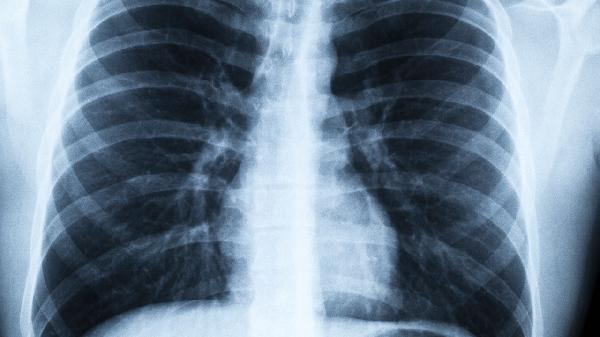

1、心肺功能水平

心脏泵血能力和肺活量直接决定氧气运输效率。长期锻炼的人,心肺功能更强,爬楼时更轻松。